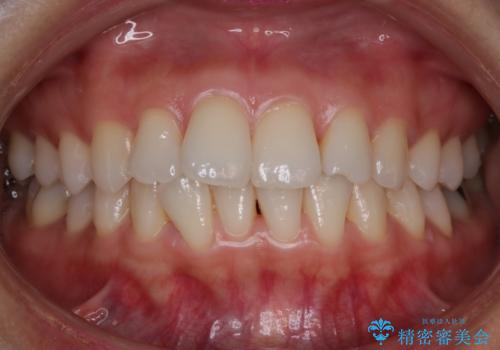

【非抜歯】前歯のガタつき マウスピースの部分矯正

- 上下の前歯の細かいガタつきの治療をご希望されて来院されました。

奥歯部分にはガタつきや噛み合わせの問題などがほとんど見られず、前歯のガタつきも軽度だったため、インビザライン ライト パッケージでの部分矯正を行うこととなりました。

今回のケースでは奥歯の噛み合わせに問題がほぼみられなかったため、前歯の位置のみに焦点を当て部分矯正を行いました。